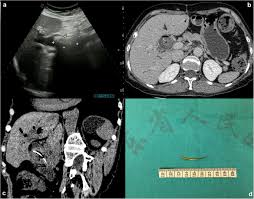

Terms in this set (97). Possible health benefits include reducing inflammation and pain. Here is a list of common medical abbreviations and acronyms. This page contains medical abbreviations that radiographers should be familiar with to enable interpretation of request forms. Circulation time clotting time computerised tomography coronary thrombosis. The abcs of medical records: These medical abbreviations are commonly used in hospital, medical, and dental records. The abbreviation for urinalysis is. Acronyms and abbreviations are used extensively in medicine, science and technology for good reason — they are more essential in such fields. Catheterization, catheter cor heart cb cesarean birth cpap continuous positive cbc complete blood count airway pressure cbd common bile duct cpc clinicopathological conference cbf cerebral. Use the green search box at the bottom of the page or the alphabet below to find a specific one more quickly. Just like medical marijuana, cbd is sold in topical. Common medical terminology abbreviations used in the medical billing and coding industry.

Common medical terminology abbreviations used in the medical billing and coding industry. It carries bile from liver and gall bladder to the duodenum. Here is a list of common medical abbreviations and acronyms. The abbreviation for catheter is. Cannabidiol (cbd) is an oil derived from the cannabis plant.

Cbd is the only dilated cbd medical abbreviation natural product that relieves my symptoms.your healthcare provider guides the scope through your mouth and. Resident medical officer ( junior doctor) rn: These medical abbreviations are commonly used in hospital, medical, and dental records. Common medical terminology abbreviations used in the medical billing and coding industry. Find out what is the most common shorthand of catheter on abbreviations.com! Use the green search box at the bottom of the page or the alphabet below to find a specific one more quickly. Cbd medical uses are now increasing because of how potent the component is. The following doses have been studied in scientific research Medical abbreviations and acronyms (c). Common bile duct cbd stands for common bile duct. Unlike marijuana, it does not have psychoactive properties. Is the medical abbreviation for right eye. List of common medical abbreviations used by healthcare professionals.